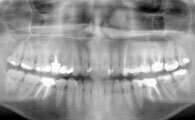

Une radio panoramique dentaire est un cliché radiographique de l'ensemble de la denture et des articulations temporo mandibulaires.